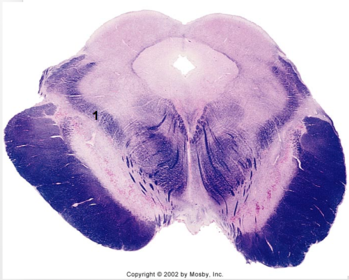

| Hypoglossal nucleus | |

| Hypoglossal nerve | |

| Dorsal motor nucleus of X | |

| Nucleus ambiguus | |

| Solitary tract | |

| Solitary nucleus | |

| ALS | |

| Medial lemniscus | |

| Medial longitudinal fasciculus | |

| Spinal tract of V | |

| Spinal nucleus of V | |

| Lateral (external, accessory) cuneate nucleus | |

| Medullary pyramids | |

| Anterior spinocerebellar tract | |

| CN IX | |

| Inferior cerebellar peduncle | |

| Inferior olivary complex | |